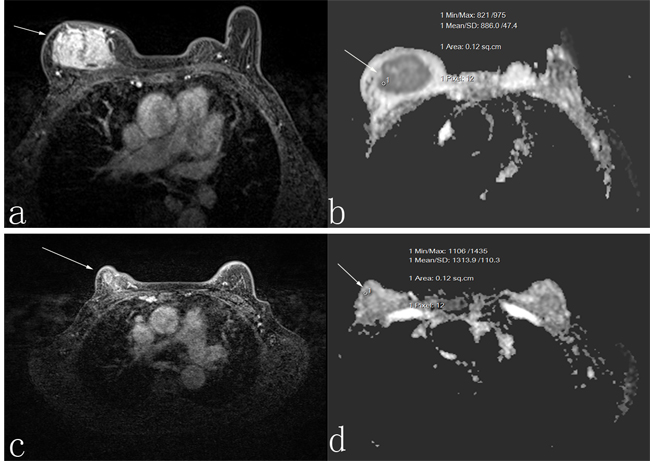

Figure 1: A 50-year-old woman who was responder with invasive ductal carcinoma. Before neoadjuvant chemotherapy, the lesion diameter was 5.5 cm in transverse contrast-enhanced T1-weighted image a. the apparent diffusion coefficient (ADC) value was 1.118 × 10-3 mm2/s b. After neoadjuvant chemotherapy, the lesion diameter was 3.4 cm in transverse contrast-enhanced T1-weighted image c., and the ADC value was 1.30 × 10-3 mm2/s d.